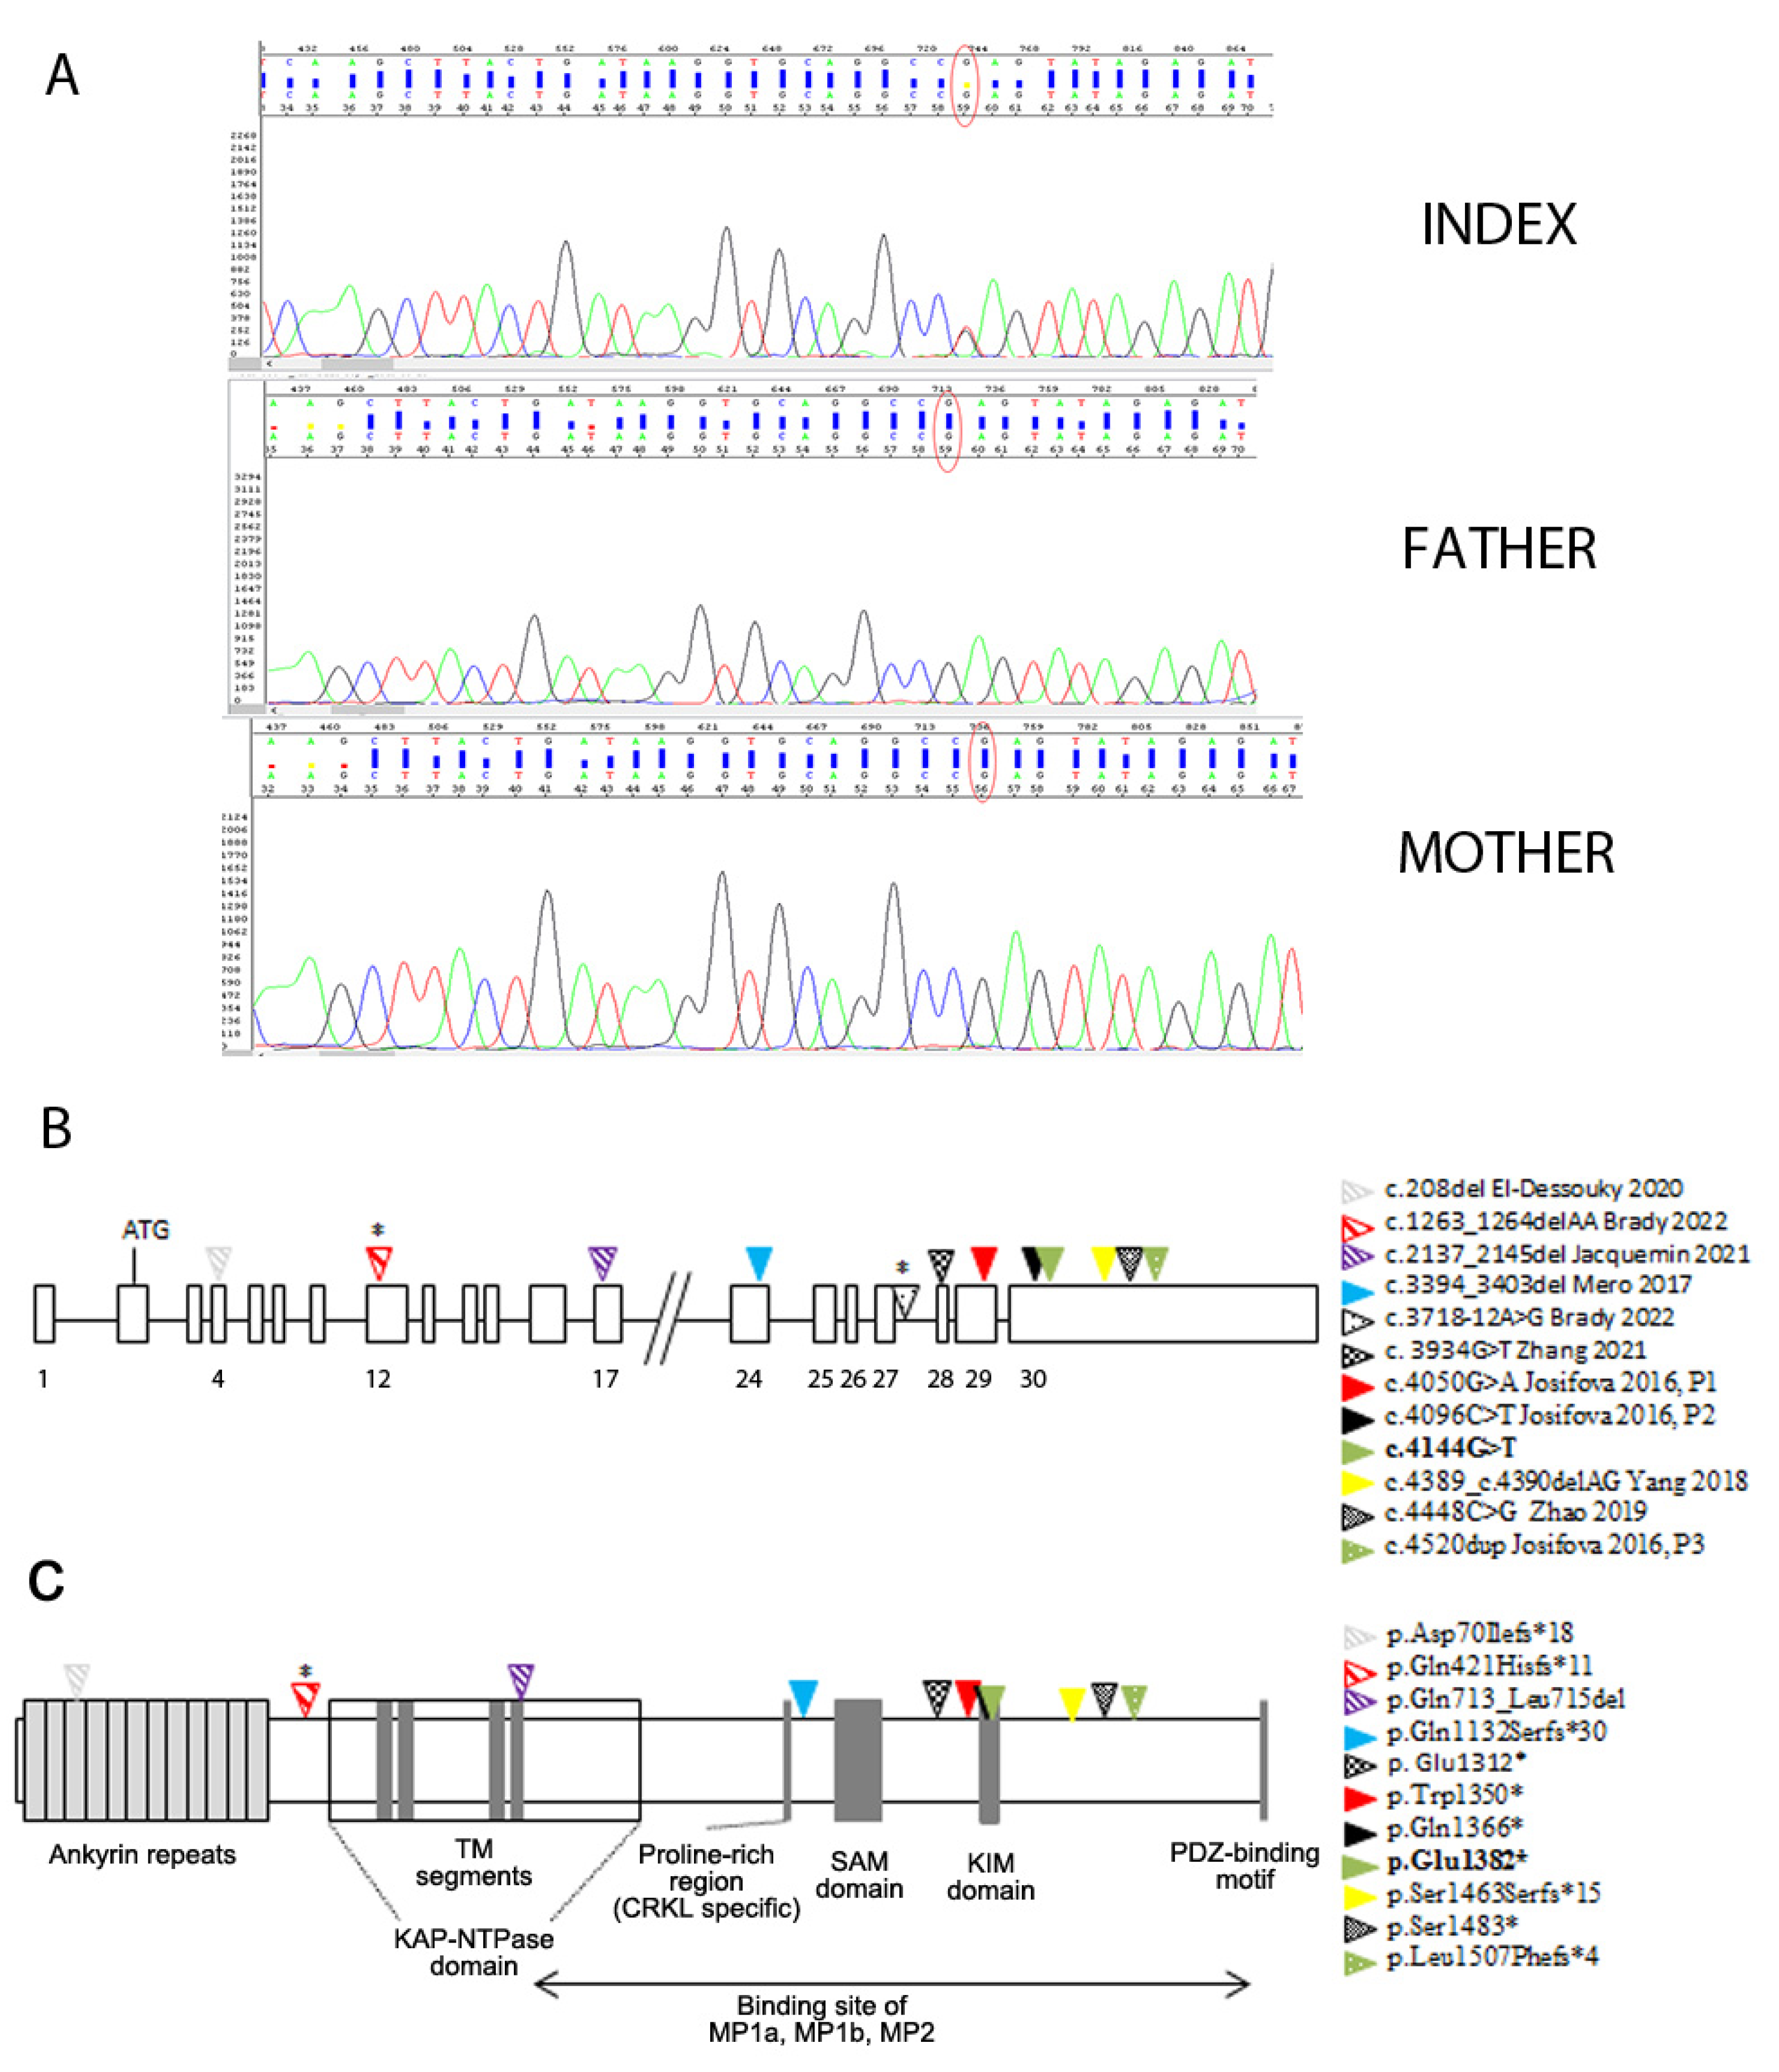

2.3. Genetic Analysis

3.2. Genetic Findings

3.3. Spectrum of Brain Malformation in Prenatal Cases and Postnatal Patients Affected by SINO

| c.4144G>T; p.Glu1382* (exon 30) | de novo | Unilateral ventriculomegaly (3rd trimester) | 22 m | Lateral ventricle enlargement, pellucidum septum agenesis, CC hypoplasia, verrticalized hippocampi, thin and dysmorphic brainstem | 18 y M | Monolateral squint, SP | Severe ID; he speaks in sentences | Early-onset macrocephaly, obesity | High forehead | Present study |

| 17 y | Also, dysmorphic and hypoplastic ALIC, partial fusion of lenticular and caudate nuclei, corticospinal tract thinning, optic chiasm hypoplasia, ↓ frontal and temporal lobe volume with cortical gyration simplification, absence of superior cerebellar peduncles decussation | |||||||||